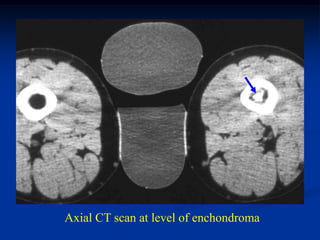

Case #587

42 year male with

combined periosteal

chondroma and

enchondroma next to

each other in femur

enchondroma

Bone scan

periosteal chondroma

Sagittal CT scan

Axial CT scan at level of enchondroma

periosteal

chondroma

CT scan

Coronal T-1 MRI

Axial T-1 MRI